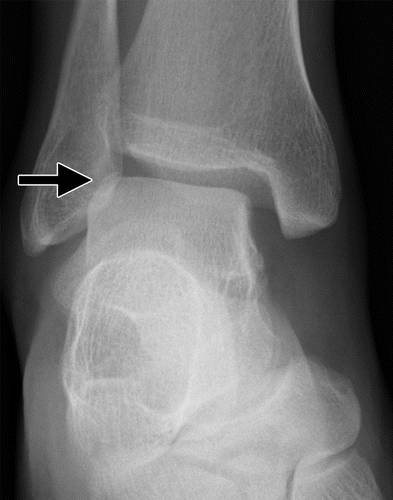

图6a Hawkins-Canale II型距骨颈骨折。 踝部的侧面放射照片(a)和矢状CT图像(b)显示了距骨后颈(a的箭头)和后部距下小平面(箭头)的脱位的垂直骨折。

II型是位移性垂直距骨颈骨折,伴有距下关节半脱位或脱位,内侧脱位比外侧脱位更常见。 胫骨和腱鞘关节保持一致(图6)。 如果脱位完成,通常存在开放性损伤。 在II型损伤中,距骨的三个血液供应源中的至少两个中断:近侧的踝颈分支(如在I型中),以及在跗骨窦和跗管的顶部进入下部的血管。 经由在距骨体的内侧表面上的血管孔进入的第三主要血源也可能受损。